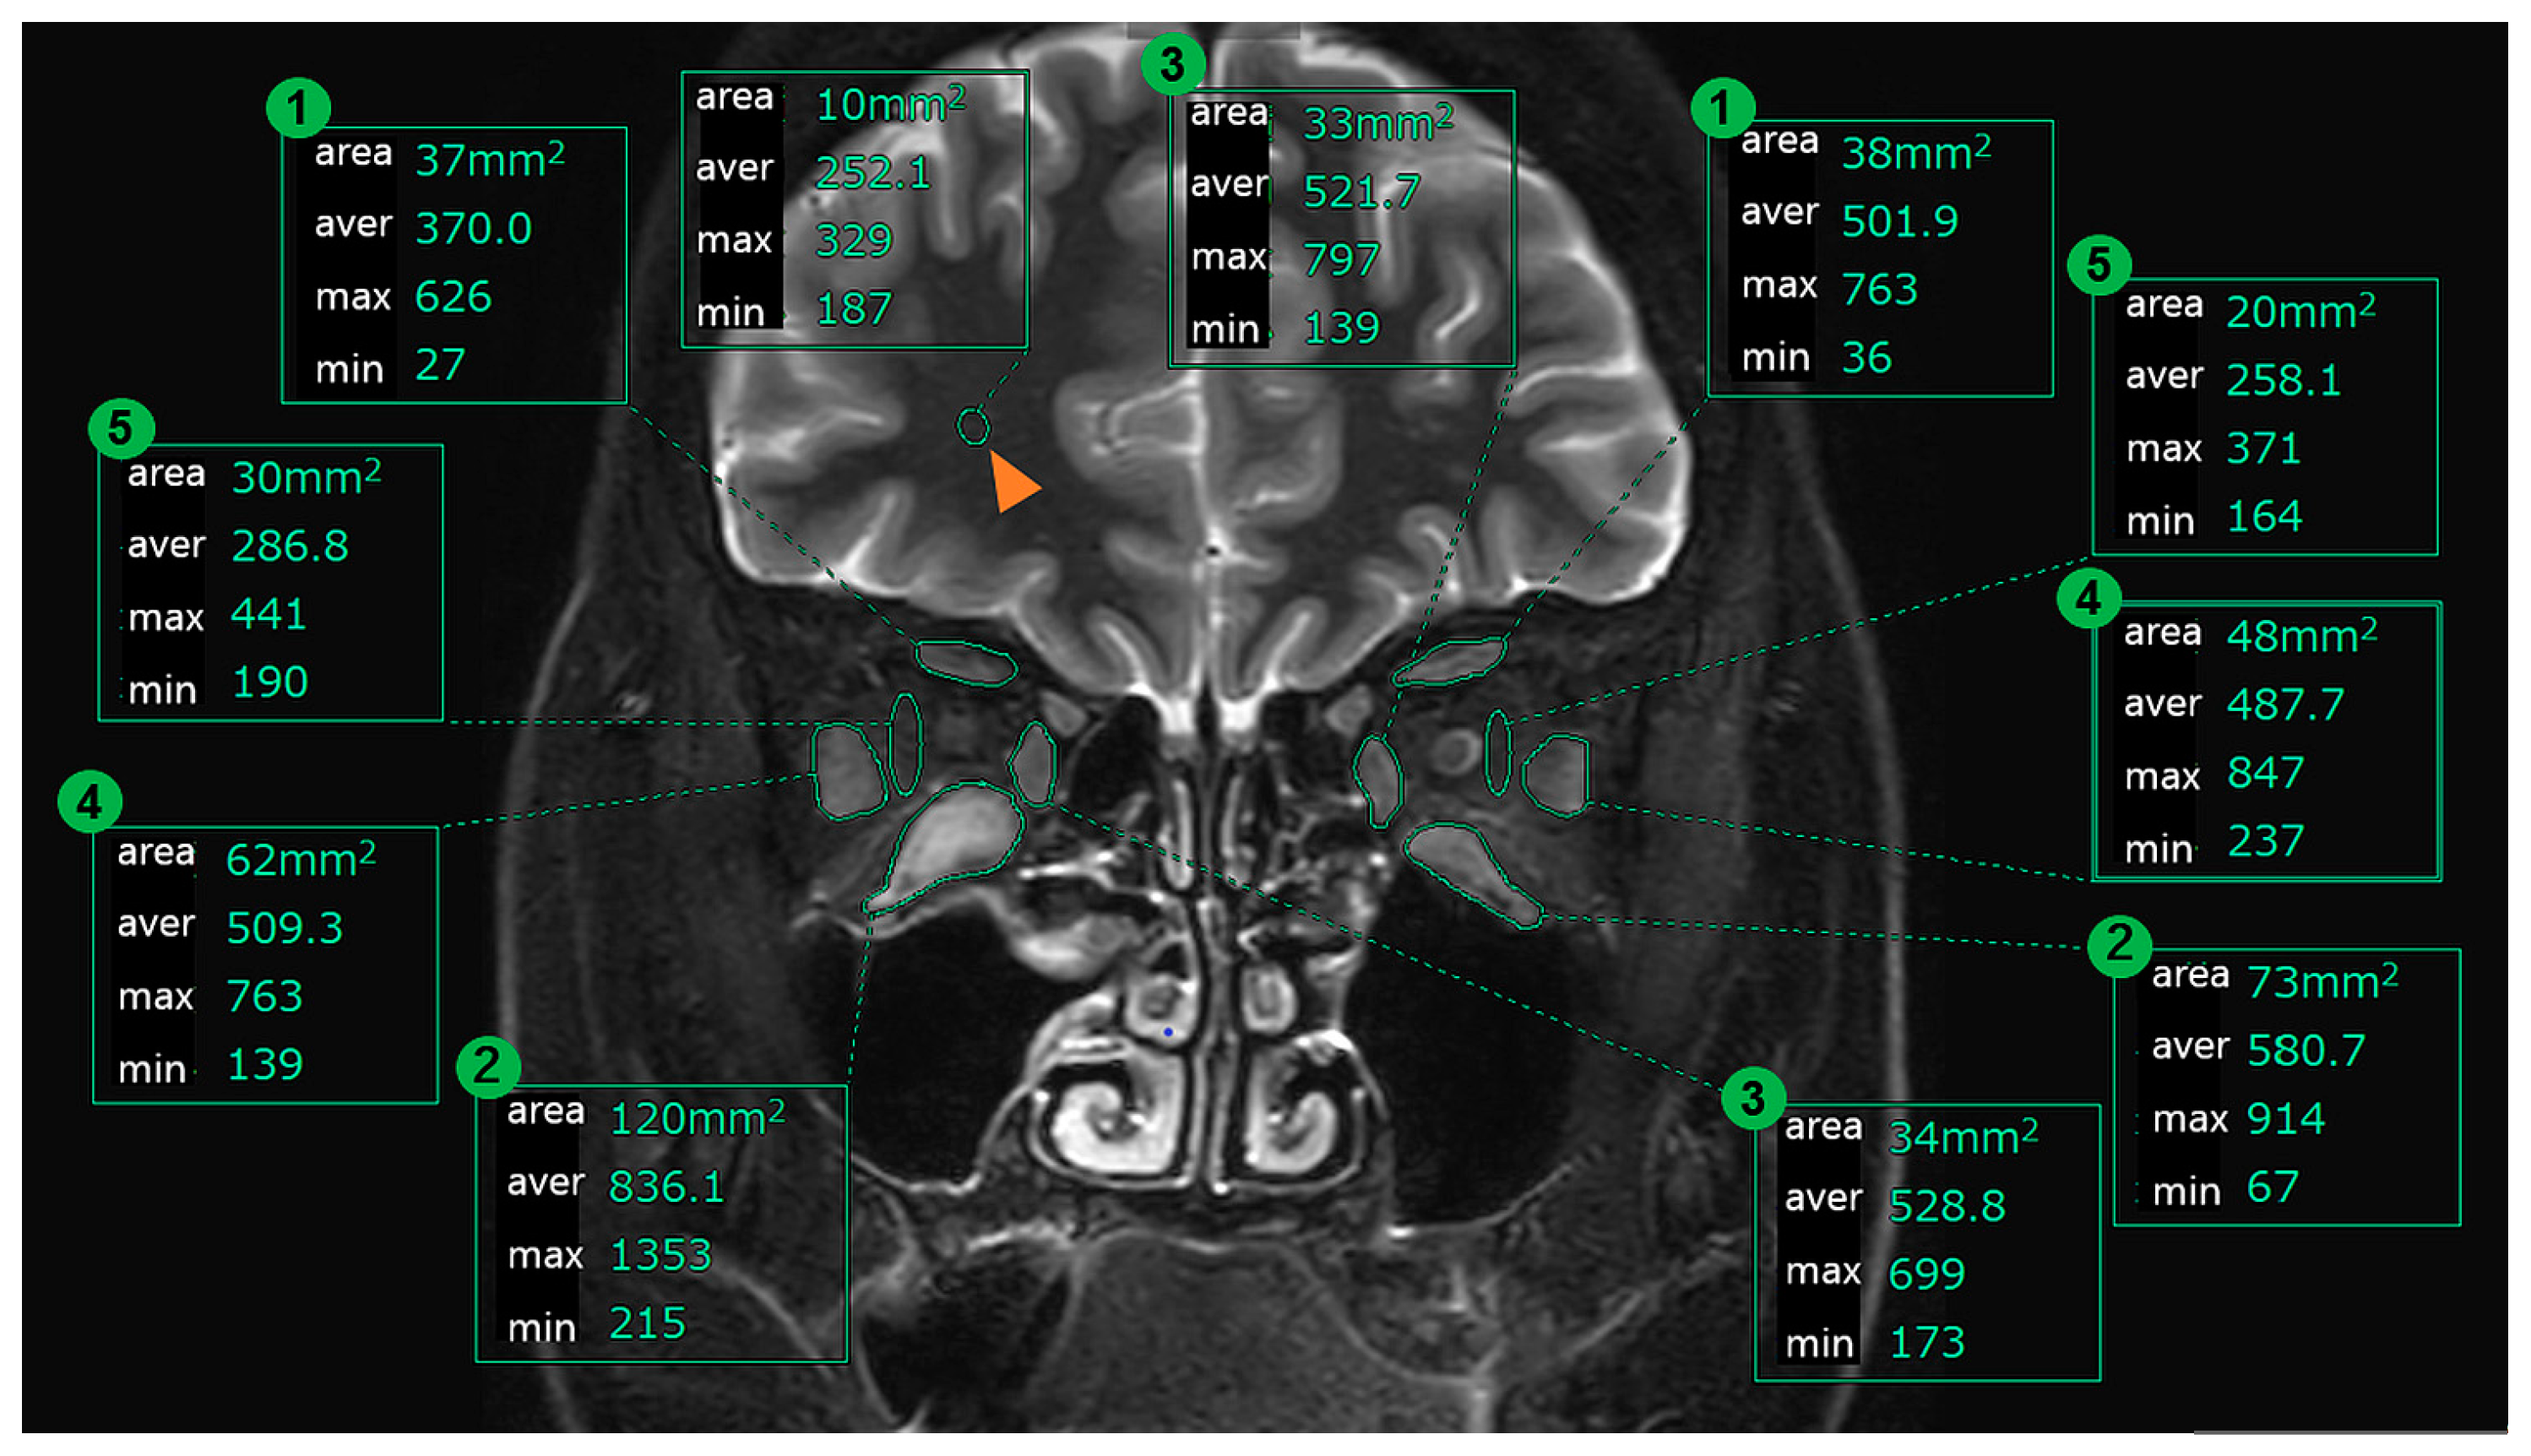

We measured the IOP, cross-sectional area, and signal intensity ratio (SIR: as explained below) of the EOMs before and after the treatment protocol, then examined the changes before and after treatment and the correlations that were observed between them. We selected both eyes in each patient. The IOP was measured using a non-contact tonometer (Nidek Co., Ltd., Aichi, Japan) in the primary position of gaze in all patients. Pre-treatment IOP measurements were performed at a visit within 1 month before and after the MRI scan. Post-treatment IOP measurements were performed at a visit within 1 month after the day of MRI scan. Orbital plain MRI examinations were performed within the several months before the treatment and within the 1-month period after the end of the treatment protocol. Coronal sections were imaged in 3 mm slices using imaging conditions that included the STIR method. The STIR method is an imaging method that suppresses the signal from the area where the T1 is shortened by making the T1 shorter than the normal IR method and additionally emphasizes both the T1 and T2 in other areas [11,12]. Higher contrasts can be obtained in areas with a lot of fat such as inside of the orbit. We selected coronal cross-sections of the images that were taken in 3 mm slices using the STIR method. Among these, we then selected coronal cross-sectional images that were taken approximately 9 mm behind the edge of the eyeball (3 slices from behind the last cross-section in which the eyeball appears). Three ophthalmologists and one radiologist (Y.H, A.S, N.M, and K.A.) evaluated and obtained the images from the areas that surrounded the EOMs (superior rectus: SRM, inferior rectus: IRM, lateral rectus: LRM, and medial rectus: MRM) and then measured the internal cross-sectional area and signal intensity. We also evaluated images from certain areas that surrounded the orbital fatty tissue between the LRM and the eyeball, then measured the signal intensity inside the area (Figure 1). We used dedicated analysis tools (Synapse Vincent, Fujifilm, Minato-ku, Tokyo, Japan). In addition, we measured the signal intensity of the white matter within a 10 mm range in the same cross-section, with definition of the SIR as presented below.

Figure 1. Coronal MRI and measurement method. Note—area: cross-sectional area (mm2), aver: average of STIR signal intensity, max: maximum of the STIR signal intensity within the selection, min: minimum of the STIR signal intensity within the selection, orange arrows: white matter, 1: SRM, 2: IRM, 3: MRM, 4: LRM, and 5: orbit fatty tissue.